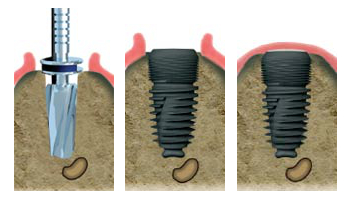

Tout d'abord le praticien doit accéder à l'os, en dégageant la gencive. Pour cela il pratique une incision à l'aide d'un bistouri, puis il décolle la gencive pour bien voir son champ opératoire. Aujourd'hui des scanners 3D reproduisant sur ordinateur l'anatomie précise des maxillaires permettent une chirurgie beaucoup moins invasive dans les cas courants (technique dite 'flapless').

L'implantologiste va, à l 'aide de forets de diamètre adpaté, préparer la place dans l'os. L'implant pénétre dans l'os en forçant légèrement. Il est ainsi stabilisé. Après la pose de l'implant va avoir lieu la phase d'ostéo-intégration. En effet l'implant, contrairement à la dent, est totalement fixe, c'est-à-dire ankylosé dans l'os. La mise en charge de l'implant est généralement différée pour permettre la phase d'ostéo-intégration (de plusieurs semaines à plusieurs mois). Par la suite, une couronne sera mise sur cet implant qui se comportera comme une racine artificielle.